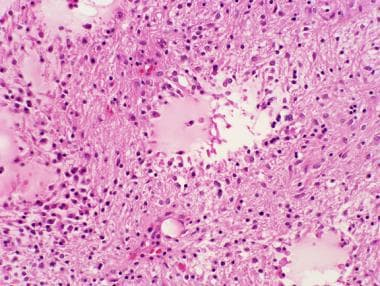

彌漫性星形細胞瘤的病理學定義和概述

浸潤性星形細胞瘤代表一組易于表現(xiàn)出腦實質彌漫性浸潤的星形細胞瘤。這種類型的膠質瘤不同于其他類型的膠質瘤,其他類型的膠質瘤表現(xiàn)出更局限的外觀,并且它們較常被邊緣的反...